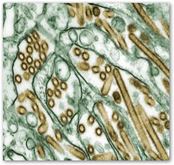

Dr. Geoffrey Ginsburg, director of Duke’s Institute for Genome Science & Policy, is collaborating with a team of colleagues to create a gadget that can detect viral infection hours before the sniffles. Between 2006 and 2009, his team made rapid strides in identifying 30 genetic markers, found through blood samples, that are activated by a virus.

They’ve since moved to human trials, testing 80 people in four studies. Healthy participants were exposed to three different viral strains. Their blood, saliva and urine were then tested for “viral specific signatures,” that would characterize illness.